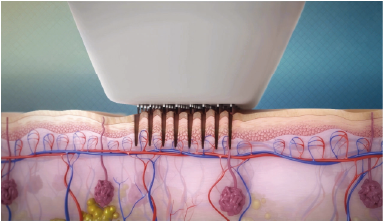

採用嶄新的納米分段式射頻及智能掃描技術,能量最高可達真皮層,從而透過熱力刺激 膠原蛋白增生。療程安全有效地重塑皮膚組織,改善各種皮膚問題,如痤瘡疤痕、深層皺紋、色素、 毛孔粗大、妊娠紋和膚色不均等。

同時產生消蝕及熱凝結點能量可穿透至皮膚500微米深度刺激膠原蛋白收縮及合成 微創傷口周邊留有完好組織,加速癒合

獨有治療模式選項,靈活控制消蝕和熱凝結比例 能量獨立傳送至每個納米電極治療後效果均勻,恢復期短

治療頭

發放納米點陣式射頻TM能量

支援SmartScan智能掃描TM

每個治療頭上共有160支納米電極

每支能釋出62毫焦耳能量

只會產生極細的微創傷口(約150X20微米)

每個專利治療頭支援高達700次脈衝,並深入皮下高達500微米

治療範圍大,痛感輕微,恢復期短